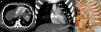

A) Reconstrucción proyección de intensidad máxima (MIP) axial de la TC en la que se identifica una hipertrofia de la arteria frénica inferior izquierda (flechas rectas). Nótese el ovillo vascular en el segmento inferior de la língula (flecha curva). B) Reconstrucción MIP coronal de la TC en la que se visualiza una hipertrofia de una rama de la arteria mamaria interna izquierda en la superficie lateral del mediastino (flechas cortas) y una hipertrofia de la arteria frénica inferior izquierda (flecha larga). Nótese el ovillo vascular en la língula (flecha curva) y la arteria pulmonar de drenaje (cabezas de flecha). C) Reconstrucción 3D (volume rendering) de la TC de tórax en la que se aprecia mejor la fístula entre las arterias sistémicas (rama de la arteria mamaria interna izquierda, flechas cortas; arteria frénica inferior izquierda, flecha larga) y una arteria pulmonar en la língula (cabezas de flecha). La flecha curva señala el ovillo vascular que comunica los 3 vasos.

Presentamos el caso de un paciente asintomático de 43 años con antecedentes personales de un sarcoma sinovial del miembro inferior derecho tratado 2 años antes en el que una TC de seguimiento detectó una fístula entre 2 arterias sistémicas no bronquiales (una rama de la arteria mamaria interna izquierda y la arteria frénica inferior del mismo lado) y una arteria pulmonar del segmento inferior de la língula (fig. 1). No se observaron lesiones pulmonares que típicamente se asocian a una hipertrofia de arterias sistémicas de tórax, como la presencia de bronquiectasias, anomalías del desarrollo pulmonar (secuestro pulmonar), atresia de la arteria pulmonar, o el tromboembolismo pulmonar crónico. Dada la ausencia de síntomas se desestimó realizar una embolización de las aferencias arteriales sistémicas.